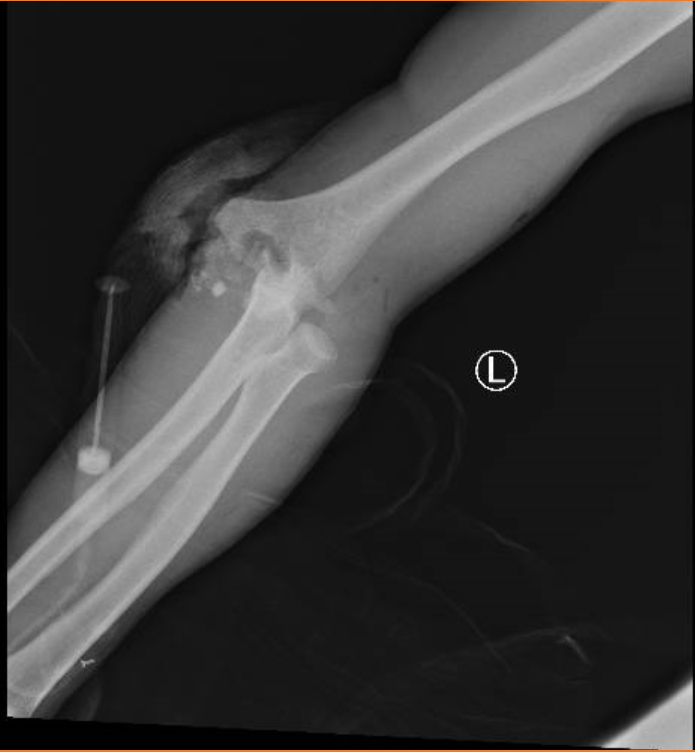

經歷過左肘關節脫位閉合復位術、左肱骨骨折切開復位外固定術、左上肢外固定架固定、雙肘關節韌帶修補術、肘關節穩定術、肘關節游離體摘除術、肘關節松解術等十多項手術后,劉先生擺脫了骨折、脫位帶來的疼痛困擾。可高處墜落帶來的肱骨滑車關節面丟失,且常規內固定無法讓他的手肘正常彎曲。劉先生想要通過進一步治療改善生活質量。

得知了劉先生訴求,創傷骨科立即為患者進行進一步檢查,并組織了科內專家進行手術評估和治療方案的討論,手術團隊最終決定為劉先生行全肘關節置換手術。由于患者雙肘關節損傷嚴重,給手術帶來了不小的挑戰。為了確保手術的萬無一失,團隊在術前開展了多次會診和手術方案討論,制定了一整套詳細周密的手術方案和應急預案。

全肘關節置換手術主要通過肘關節置換,來幫助患者恢復肘關節功能,保持肘關節屈伸達到0~135°,并恢復肘關節旋轉功能,以滿足日常生活的需要。手術當天,在醫院副院長石展英、創傷骨科副主任王棟棟的帶領下,手術團隊依次為患者松解左肘關節、游離肱三頭肌及肘肌、切除關節滑膜、摘除游離體、取出阻擋的肱骨小頭內固定、充入骨水泥至肱骨髓腔內,插入組合好的人工肘關節柄部等一系列精細的操作。憑借著豐富的臨床經驗和扎實的操作功底,全肘關節置換成功,手術順利完成。